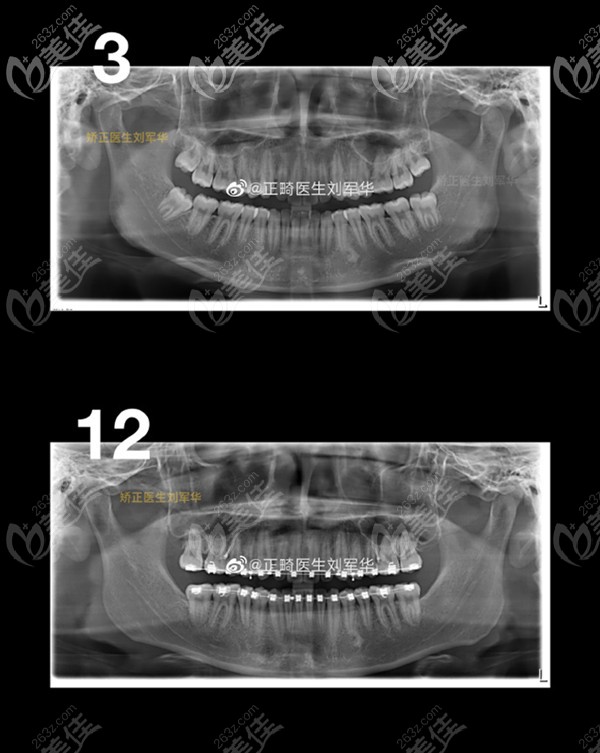

我一直知道自己牙齒長得不是特別的整齊,直到去福州登特口腔做了檢查,拍了ct才知道我這可不是一般的牙齒擁擠,而是開唇露齒,上下牙列輕度擁擠,牙弓偏尖圓形,前牙深覆合深覆蓋。

但是我爸媽堅決不同意拔牙治療,要拔只能拔掉智齒,于是正畸醫(yī)生經(jīng)過幾番思考和我們討論,定下的方案是種植支抗釘輔助遠(yuǎn)移上頜全牙列,拔掉智齒,并佩戴自鎖緊縮矯正器。

支抗釘聽起來嚇人,但在嘴里存在的時間久了就感覺不到了,當(dāng)時經(jīng)過經(jīng)過五個月的遠(yuǎn)中移動治療,上頜磨牙的牙冠遠(yuǎn)移了3.78mm,牙根遠(yuǎn)移了3.2mm,效果還是挺明顯的。

轉(zhuǎn)眼我都快21歲了,看了ct對比,我才感覺到這三年的“苦”沒白吃!牙齒整齊的特別明顯,也不擁擠了。